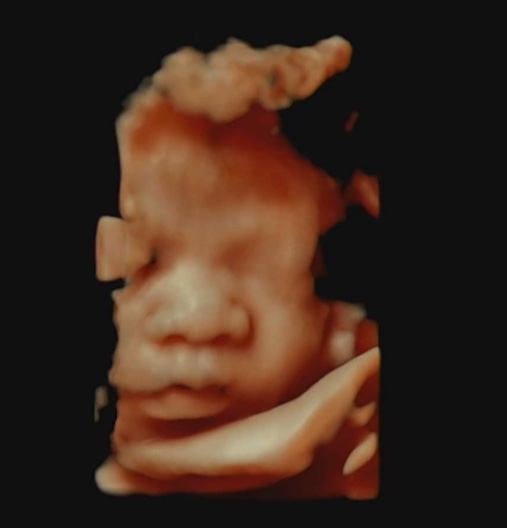

이대서울 막달검사 후기

36주5일 막달검사하고 왔어요. 36주에 진입하니 가진통이 오더라구요. 기분나쁜 생리통 정도의 통증…? 참...